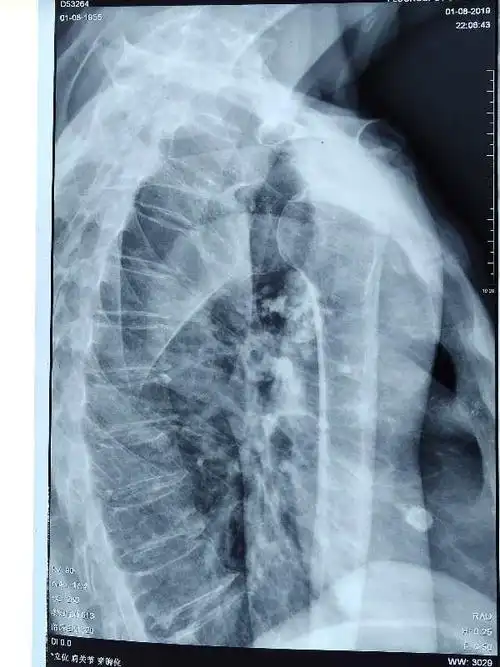

肩关节的摄影体位-素问文库

肩关节x线检查特殊体位_原作